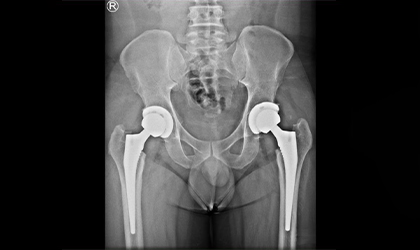

Bilateral Knee Replacement Case Study

Independent, Pain-Free, Walking

This 68 year old lady has a condition called protrusio where the socket becomes weak and protrudes into the pelvis